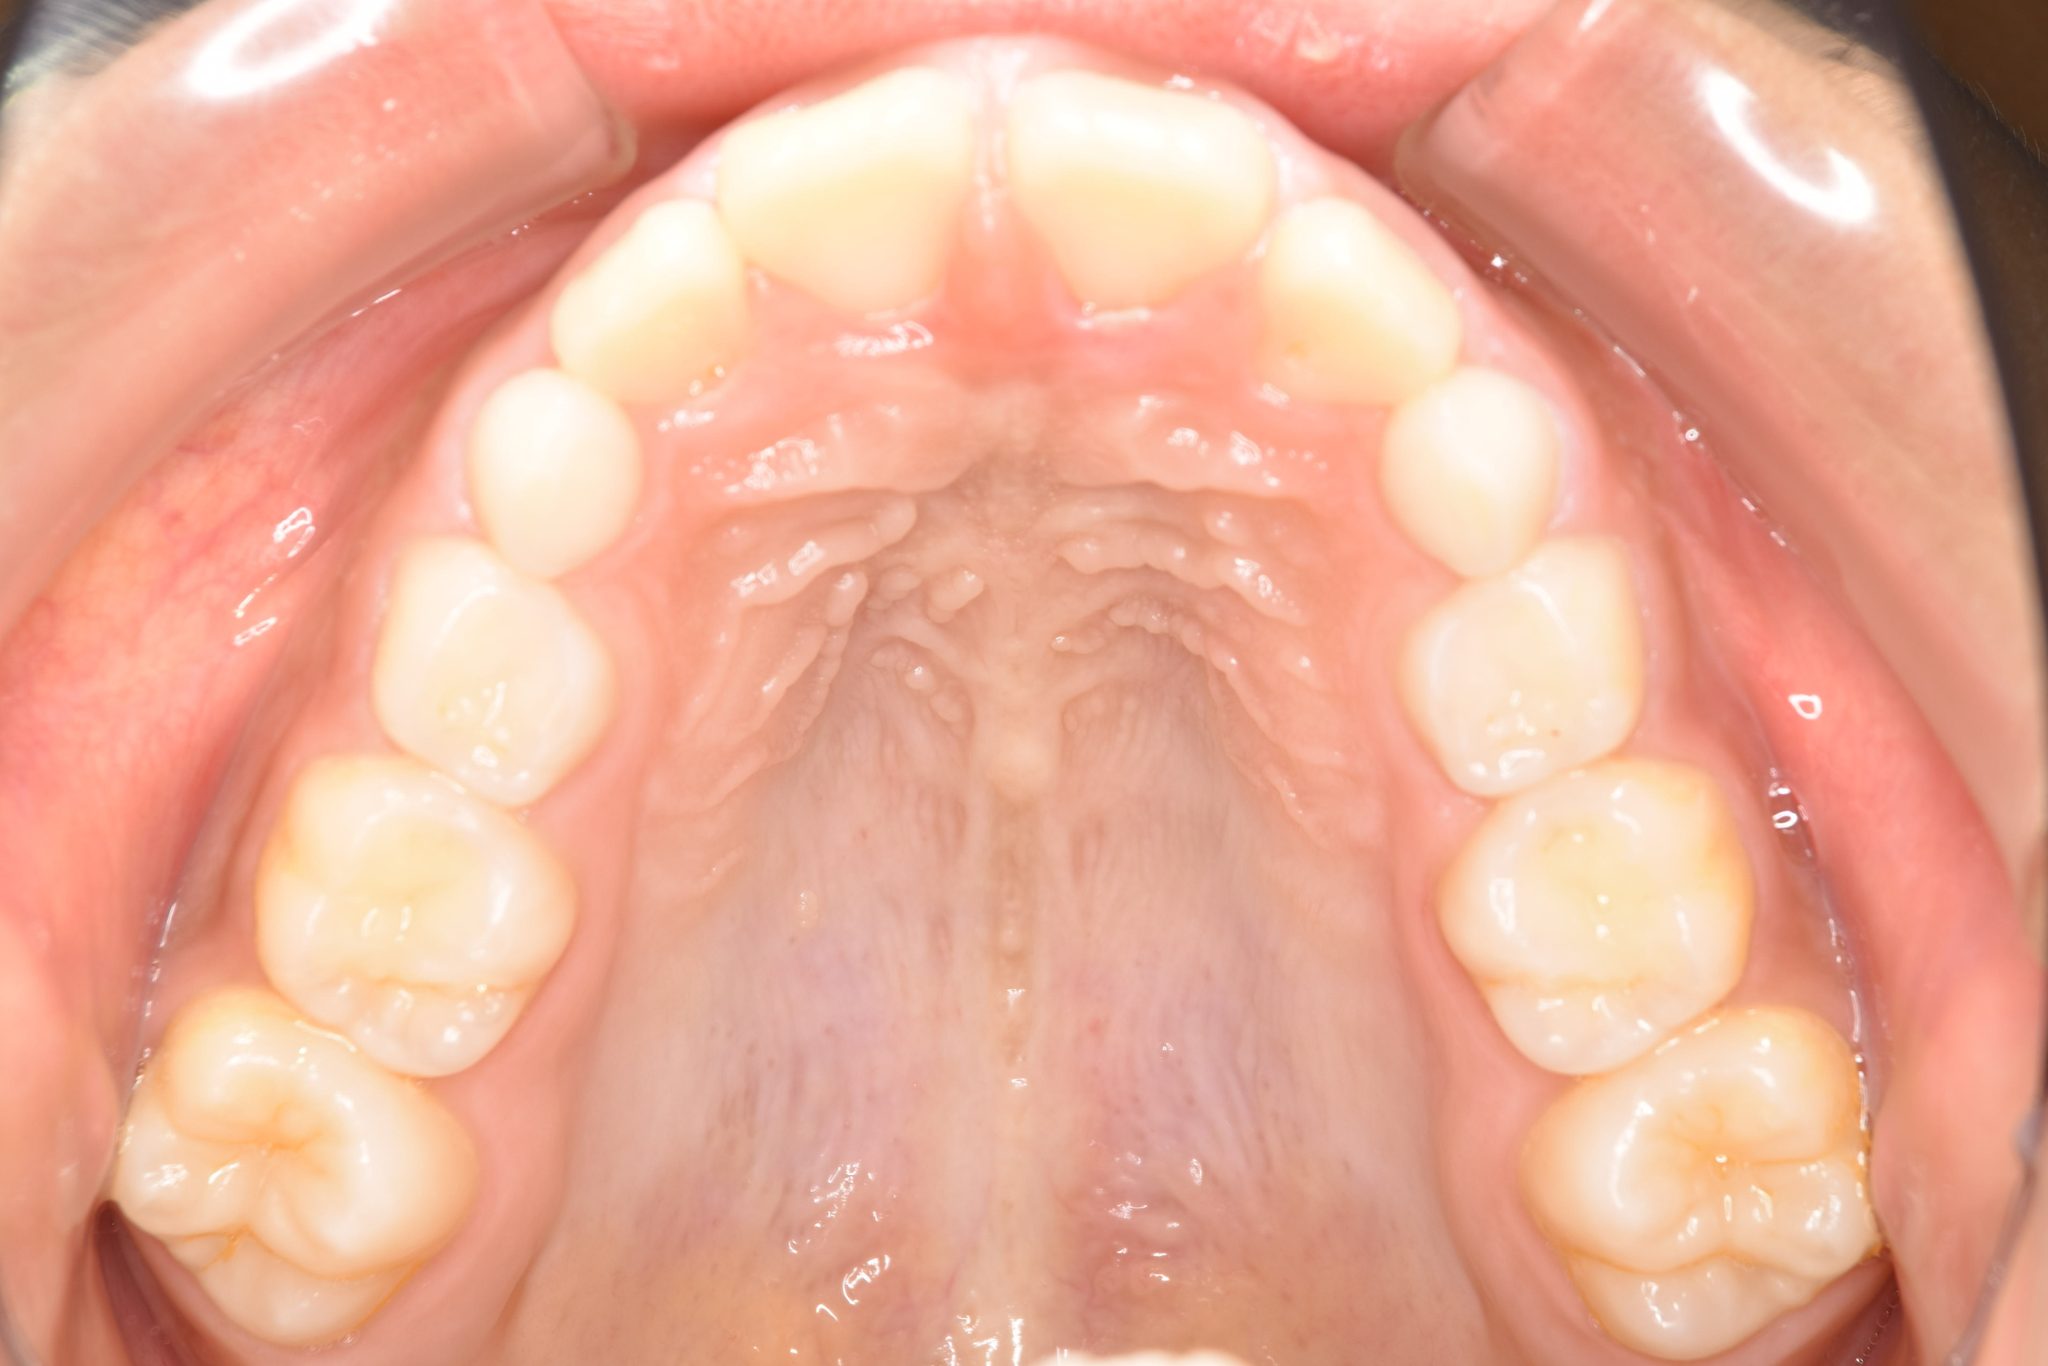

ビフォー

子どもの矯正治療|症例_547

主訴 上下の歯が接触しない

施術内容 上顎急速拡大装置と下顎リンガルアーチを用いて上下顎骨を拡大した。

その後マウスピース型矯正装置で歯牙を配列し良好な咬合を獲得した。